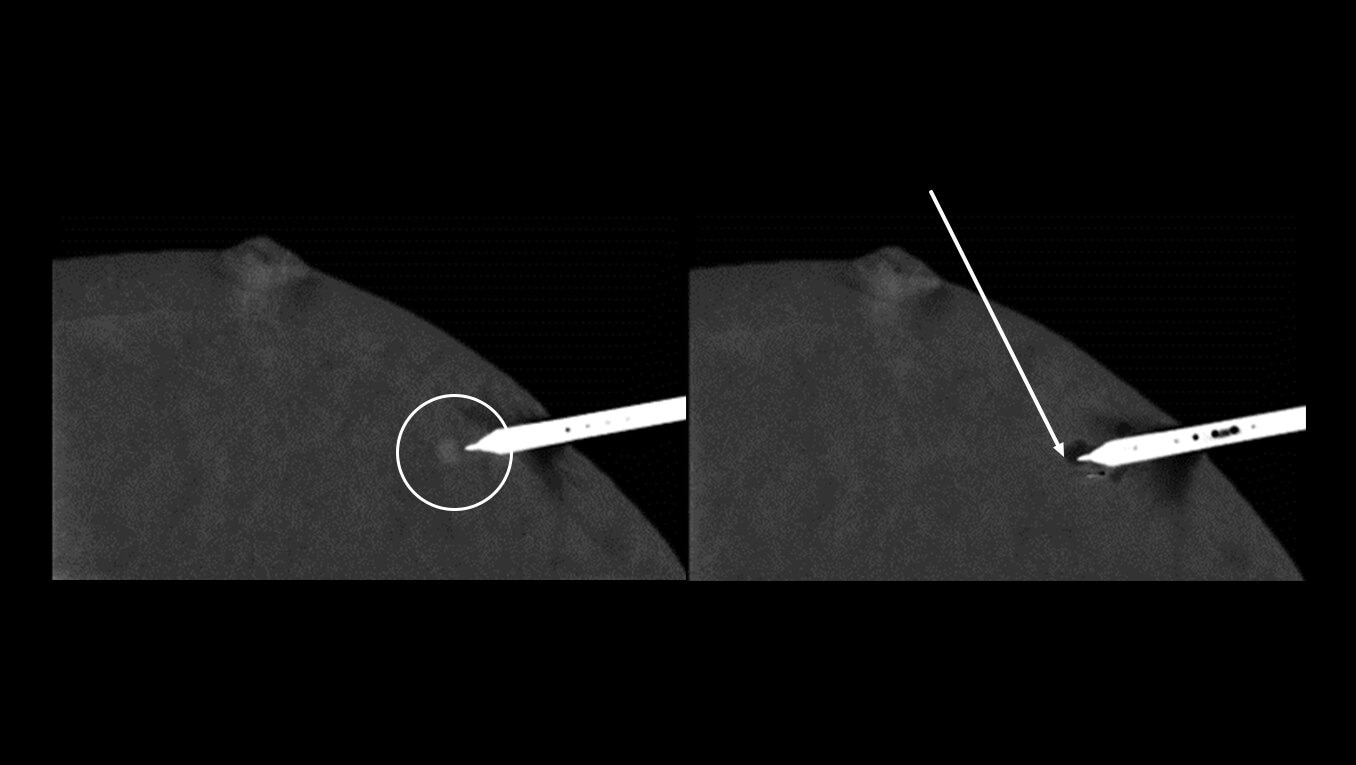

Find answers sooner

Shorten the time to biopsy and diagnosis

No more delays waiting for MRI availability or enduring lengthy 60-90 minute5 MRI-guided breast biopsy procedures. CEM guided biopsy can be performed within 15 minutes from first image to clip placement image6. A shorter biopsy lead time and quicker biopsy procedure may speed up a definitive diagnosis and faster path to treatment.